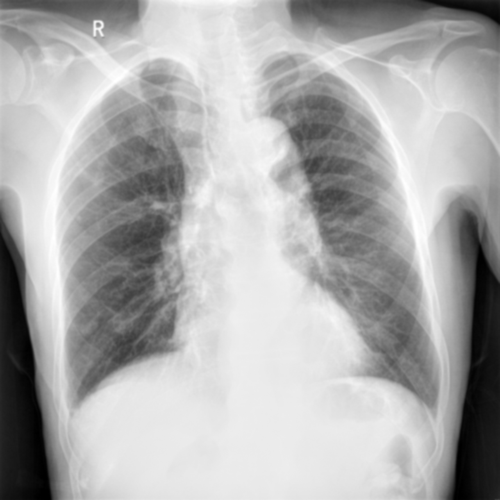

To pre-train a high-performance X-ray foundation model, the first thing we need to do is the collection of large-scale X-ray images. Therefore, a large-scale and high-resolution dataset that contains X-ray medical images is collected for the pre-training. Some representative samples are visualized in Fig. 3.